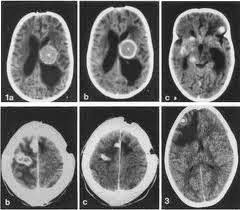

Jadi,harus dilakukan tindakan yang tepat untuk menanganinya, Salah

satunya adalah dengan melakukan CT scan. Dengan melakukan CT scan anda

bisa melihat ukuran kista serta bagaimana cara yang aka dilakukan dokter

untuk menangani kista tersebut.